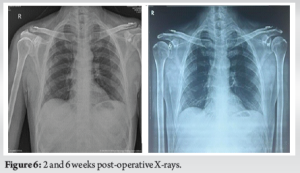

Sterile dressings were applied, and wound inspections were performed on POD 2 and 5. On the 12th POD, stitches were removed, and the patients were discharged. The patient was then followed up at 6 weeks and showed a significant improvement in his functional outcome according to the disabilities of the arm, shoulder, and hand questionnaire (specific to the upper limb) and the Oxford shoulder score. The X-ray taken at 6 weeks’ follow-up showed good fracture healing with a significant amount of the presence of bridging callus or trabeculations across the fracture site (Fig. 6).